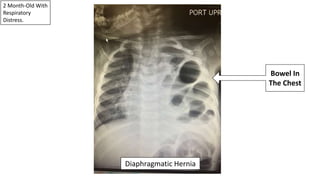

2 Month-Old With

Respiratory

Distress.

Diaphragmatic Hernia

Bowel In

The Chest